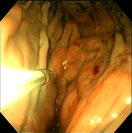

‣当院での症例紹介

異物:1円玉

異物:裁縫針

異物:梅干しの種

胃腺癌

胃瘻チューブ設置

炎症性ポリープ

炎症性ポリープ⑵

気管虚脱

気管支腫瘍

気管腫瘍

喉頭腫瘍

食道内異物回収後

鼻腔内腫瘍(犬)

鼻腔内腫瘍(猫)

慢性腸症(犬)

慢性腸症(猫)